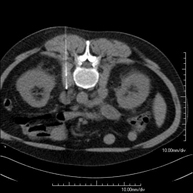

- Abdominal and pelvic CT

Diagnostic test that consists of obtaining high-definition anatomical images (bone structures, vascular structures, liver, pancreas, gallbladder, kidneys, adrenal glands, spleen, small and large intestine, bladder, uterus and ovaries, prostate and seminal vesicles, ureters, etc.) using CT (computed tomography) equipment. Most studies require the use of iodinated contrast.